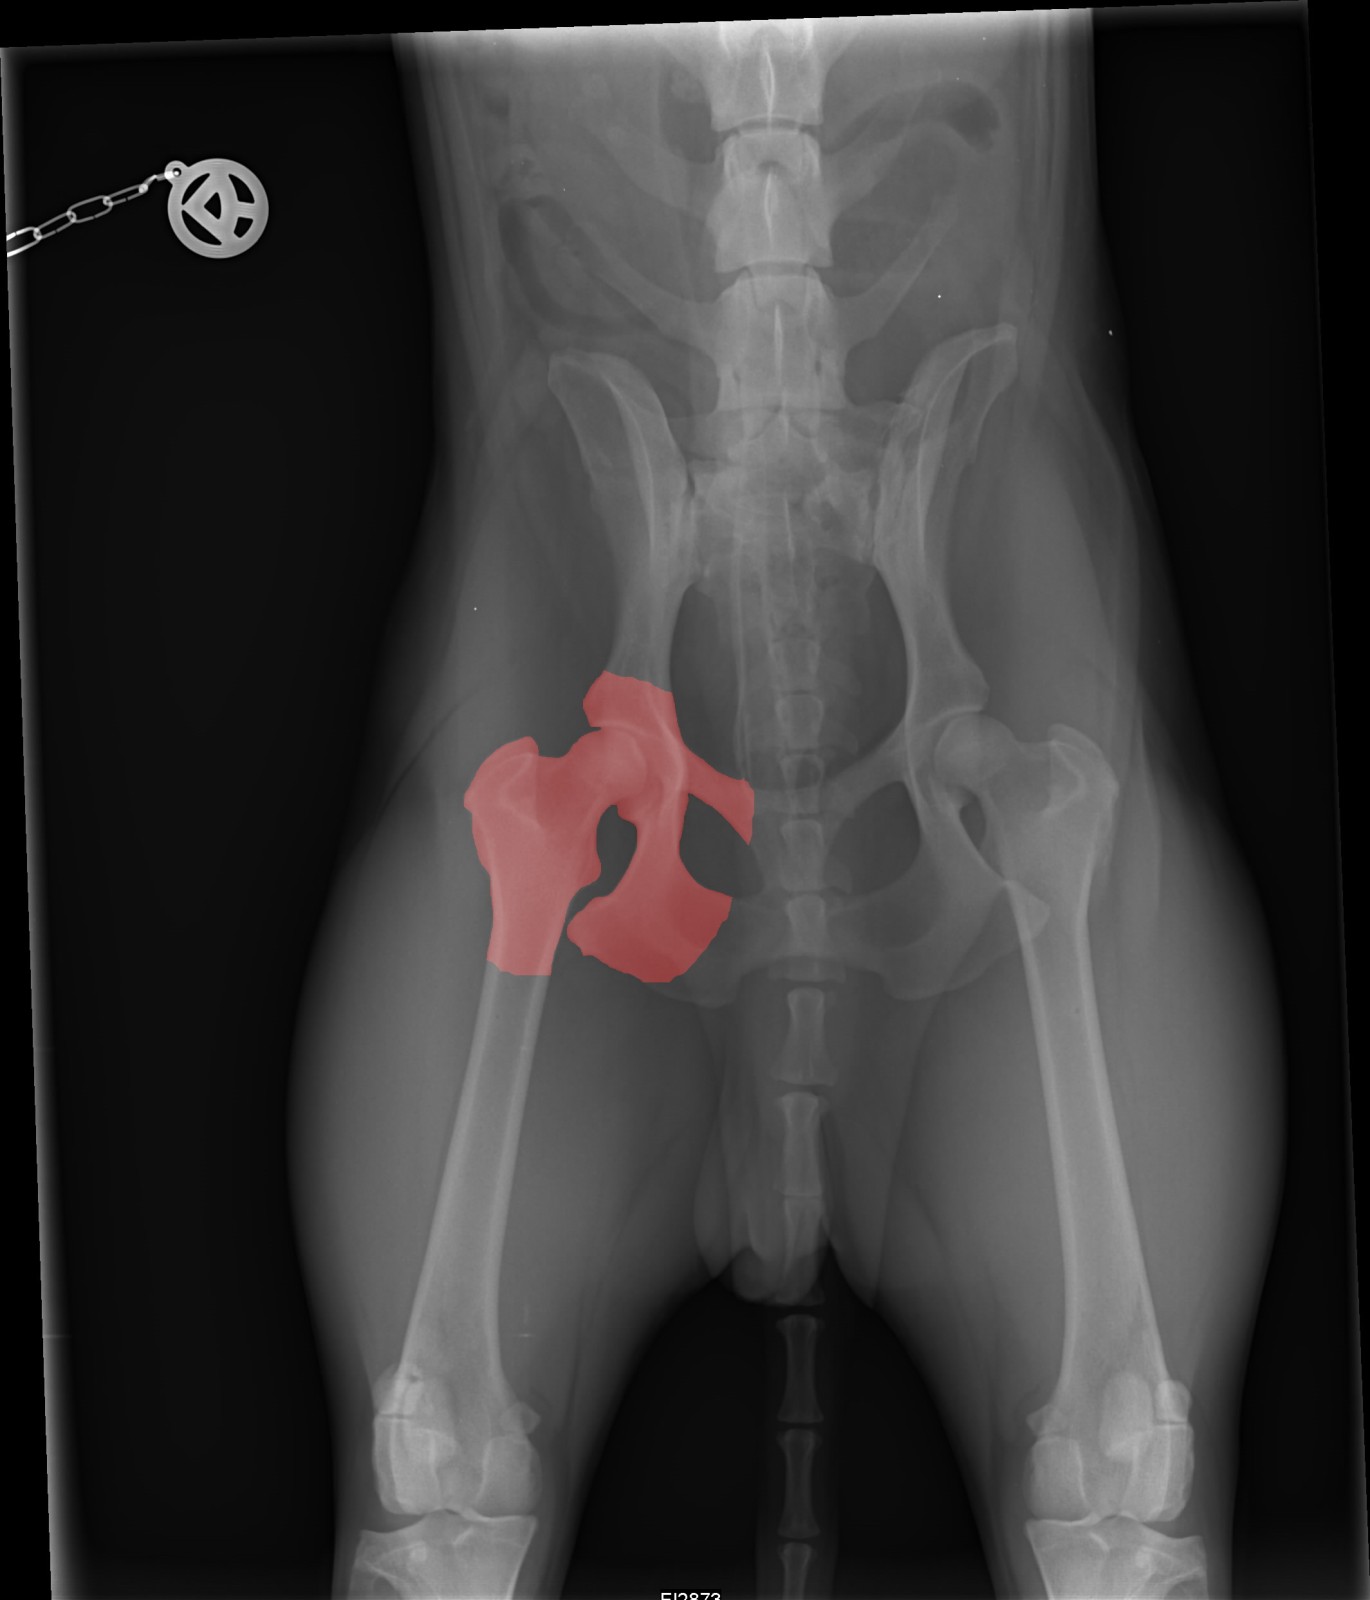

Diagnose:

Der Hund muss unter Vollnarkose geröntgt werden